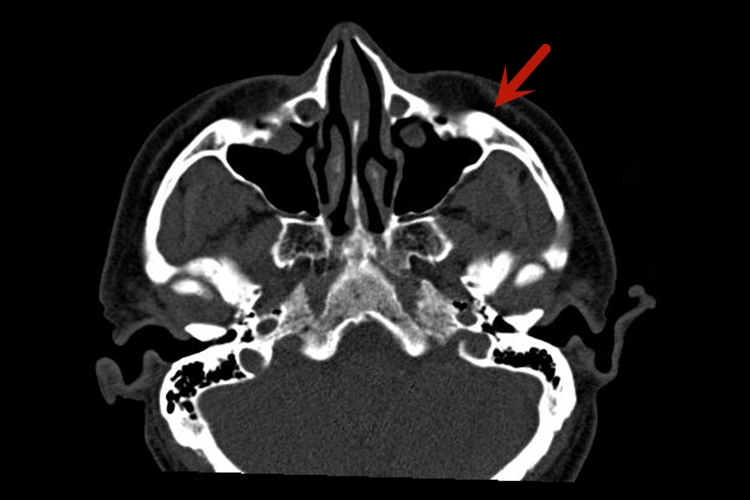

上颌骨:上颌骨分为体部和4个突起。体部包含上颌窦,窦口开向鼻腔,4个突起为额突、颧突、腭突及齿槽突,两侧腭突与腭骨水平板组成硬腭。

颌面部CT对于颌面部组织病变的发现、诊断及其范围确定等,均有重要价值。比如通过CT下腮腺腺体形态、大小和密度的变化,可以判断病变的部位及蔓延范围,良性肿瘤与恶性肿瘤的鉴别,以及腮腺外肿瘤的侵犯。

若有良性肿瘤,其CT特征是肿块多呈类圆形,边缘光整,密度均匀,其中血管瘤有明显强化。恶性肿瘤的形态多不规则,边界模糊,密度不均匀,肿块内常有出血、坏死或囊变,常侵犯周围软组织及脂肪间隙,颅底骨质破坏及淋巴结转移。